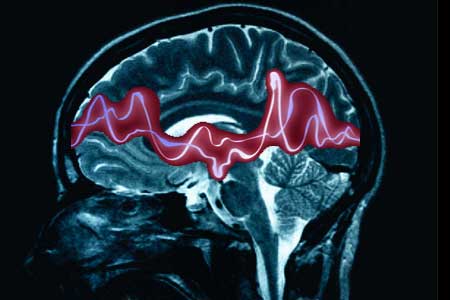

Una combinación de dos medicamentos, la lamotrigina y el valproato, es más eficaz en el tratamiento difíciles de controlar de epilepsia que otros regímenes anti-epilépticos, según un informe de la Universidad de Washington que será publicado en línea esta semana en Neurology, la revista de la Academia Americana de Neurología.

En una gran escala, estudio retrospectivo de una población de pacientes con muy difíciles de controlar la epilepsia, los investigadores descubrieron que sólo la lamotrigina / régimen de tratamiento con valproato, de las32 combinaciones de fármacos estudiados, disminuyó significativamente la frecuencia de crisis en este grupo.

Esta combinación específica reduce la frecuencia de crisis a la mitad, en promedio, en comparación con otros regímenes. A pesar de que rara vez se produce una completa libertad de convulsiones, la combinación fuesuperior a los demás en la reducción del número de crisis convulsivas pacientes experimentaron.